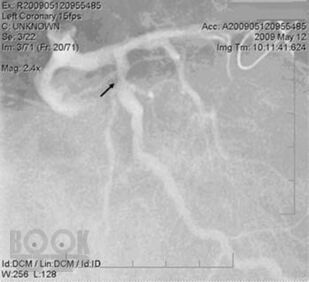

Часть II Кардиореабилитация на конкретных примерах описывает наиболее распространенные сердечные заболевания: ишемическая болезнь сердца с сахарным диабетом II типа или без него, инфаркт миокарда, случаи сердечной недостаточности в относительно стабильных условиях, при наличии или отсутствии устройств, контролирующих работу сердца и т.д.

- Представлены варианты диагностики и лечения разных заболеваний (коморбидные состояния, инфаркт миокарда, стенокардия, коронарное шунтирование, имплантация кардиостимулятора или водителя ритма, врожденный порок сердца, поражение периферических артерий) на примере репрезентативных клинических случаев.